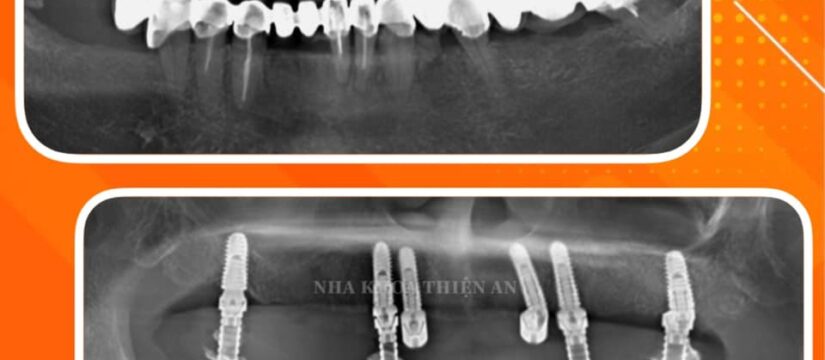

Cấy implant toàn hàm All-on-6 cho cô H. (60 tuổi).

Tình trạng trước điều trị: cầu răng sứ dài lung lay đã lâu, kiểm tra thấy các chân răng còn lại mục nát, gãy sâu dưới nướu, nha chu tiêu xương nặng không còn khả năng bảo tồn …

All-on-6 implant for Ms. H. (60 years old).

Condition before treatment: long porcelain bridge has been loose for a long time, checked that the remaining roots are rotten, broken deep under the gums, periodontal bone loss is no longer able to preserve …